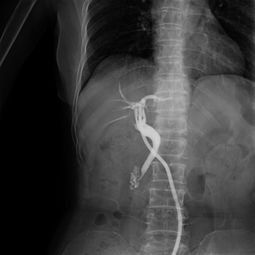

病情分析:您好,造影一般在月經(jīng)干凈后第三天至第五天做,做之前最好是不要性交. 意見建議:做完造影最好是隔一個月再計劃懷孕,因為做的時候有照X光.祝心情愉悅.病情分析: 您好,對于檢查輸卵管是否阻塞通暢,最好是做:動態(tài)數(shù)字化子宮輸卵碘油造影響,它是 在全程無痛的情況下完成的,對于輕微阻塞的輸卵管能起到疏通治療的作用.并且患 者可以在第一時間看到自己的輸卵管與宮腔的形態(tài)..若是嚴(yán)重阻塞則需要手術(shù)來疏通意見建議: 1,必須在月經(jīng)干凈3-7天后檢查,因為此期子宮內(nèi)膜較薄,不易造成子宮內(nèi)膜異位癥. 2,檢查之前禁止性生活. 3,在造影檢查過程中注射造影劑后,必須拍片兩次方能確定診斷您好:造影的檢查要在月經(jīng)干凈后的3-7天檢查,輸卵管分間質(zhì)部,峽部,壺腹部,傘端.輸卵管粘連,堵塞,上舉屬于器質(zhì)性的改變,藥物治療沒有明顯的改變,手術(shù)治療效果明顯,一般可采取宮腔鏡,腹腔鏡,輸卵管鏡治療,創(chuàng)傷小,恢復(fù)快可以在專家的指導(dǎo)下盡快受孕.y病情分析: 您好,很高興為您解答意見建議:造影一般在月經(jīng)干凈后第三天至第五天做,做之前最好是不要同房. 做完造影最好是隔一個月再計劃懷孕,因為做的時候有照X光. 生活護(hù)理:祝您早日康復(fù)身體健康您好: 受孕是個很復(fù)雜的生理過程.它要求精卵相合形成受精卵,最后著床于宮腔.除了要有正常的精子,卵子和適當(dāng)?shù)淖訉m內(nèi)環(huán)境外,使精子,卵子能夠相遇并順利運送到宮腔也是受孕經(jīng)過中一個重要的環(huán)節(jié).這個任務(wù)是由輸卵管來完成的.如果輸卵管有炎癥,導(dǎo)致輸卵管堵塞,精子不能通過與卵子相遇造成的不孕,則稱為輸卵管阻塞性不孕.輸卵管根據(jù)形態(tài)由內(nèi)向外分為四部分:間質(zhì)部,峽部,壺腹部,傘部.在臨床上,有80%的不孕癥患者是由于輸卵管因素而造成.輸卵管阻塞常因人工流產(chǎn),自然流產(chǎn),藥流,引產(chǎn),不潔性交,盆腔感染等引起輸卵管壁粘連,充血,水腫而阻塞,導(dǎo)致精子與卵子不能夠結(jié)合,最終導(dǎo)致不孕癥.建議您到??漆t(yī)院就診,明確病情嚴(yán)重程度后在選擇合適的治療方案進(jìn)行疏通.W病情分析: 輸卵管造影前注意事項意見建議: 1,必須在月經(jīng)干凈3-7天后檢查,因為此期子宮內(nèi)膜較薄,不易造成子宮內(nèi)膜異位癥. 2,檢查之前禁止性生活.3,在造影檢查過程中注射造影劑后,必須拍片兩次方能確定診斷.。